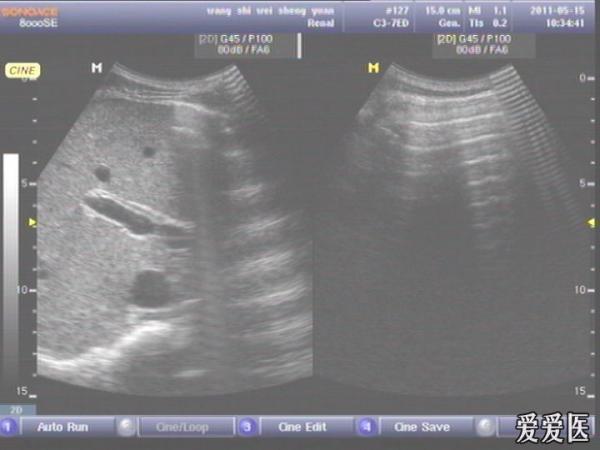

患者,男,38岁,进食后突发上腹部持续性剧烈疼痛一小时来查。超声见横膈与肝之间、上腹部皮下气体强反射回声,后伴多重反射,肝前、肝肾间隙,腹腔肠管间均可见游离无回声区。直视腹部见上腹部似板样。结合病史提示“胃肠道穿孔”。急诊手术证实。

左肝外叶的那个切面如果能看到气体回声的话,那就应该高度怀疑这个病了。好切面,好好学习,太有用了,楼主辛苦感谢感谢。